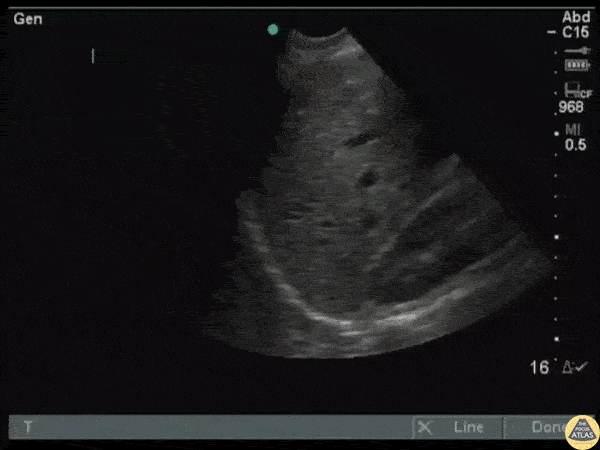

Trauma - Hepatic Laceration

Seen in the superficial region of the liver is an easy to miss hepatic laceration. Ultrasound has a low specificity for detecting solid organ lacerations. Diagnosis was confirmed via CT. Image courtesy of Robert Jones DO, FACEP @RJonesSonoEM Director, Emergency Ultrasound; MetroHealth Medical Center; Professor, Case Western Reserve Medical School, Cleveland, OH View his original post here